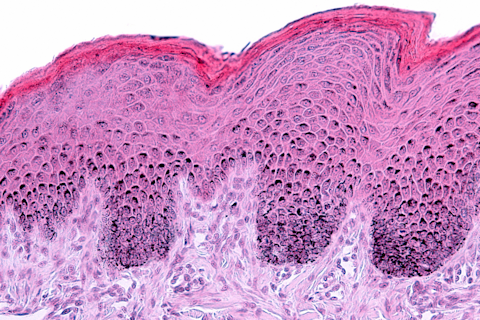

Skin Longevity From Ancient Wisdom to Modern Clinical Evaluation

Explore how non-invasive clinical tools and biomarkers advance skin longevity assessment and substantiate product efficacy.